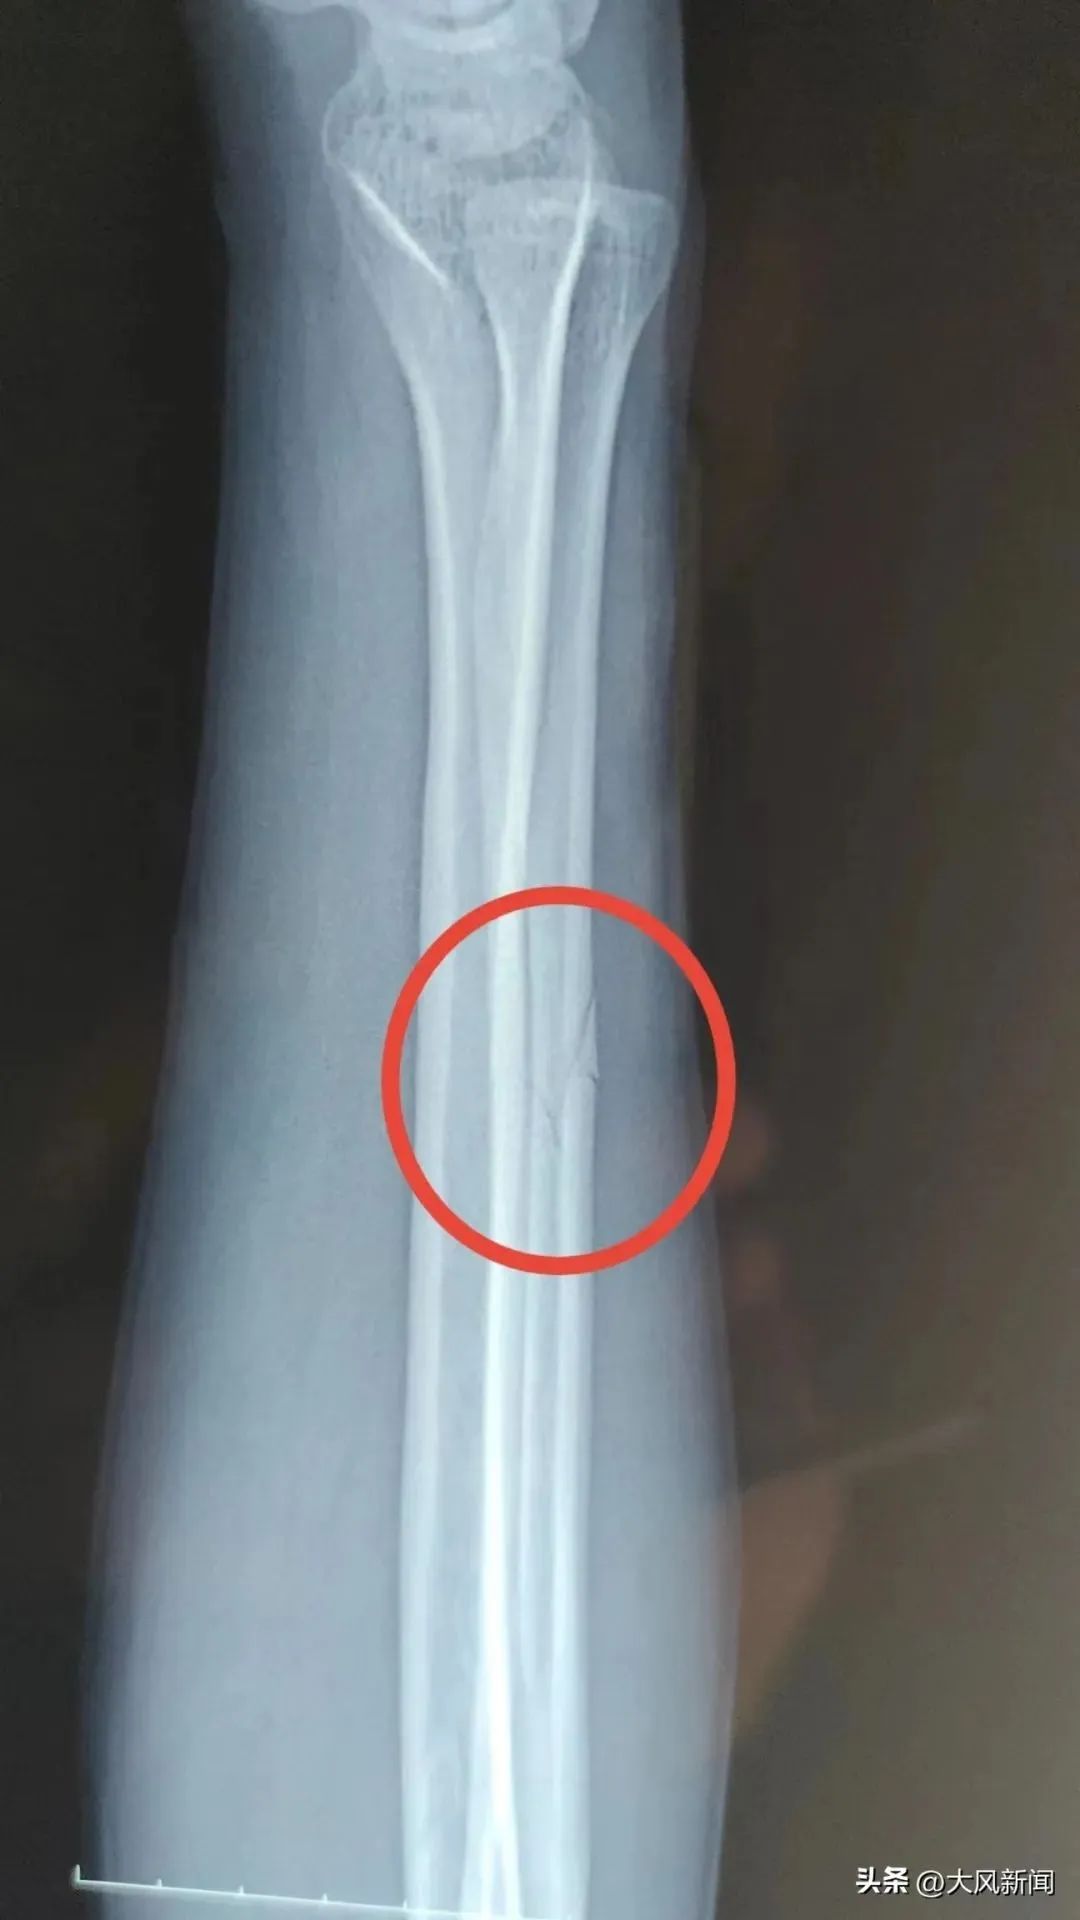

事发后宋某报了警,当晚去医院检查并打了石膏,医生让先回家观察。宋某系第二天右臂痛疼难忍,于2022年11月13日下午6时自行前往丹凤县医院检查。经诊断右尺骨骨折,外伤性头疼。

在宋某出院两个月后,2023年2月13日,商洛市丹凤县公安局龙驹寨派出所向宋某出具了第一次伤情鉴定报告。宋某人体损伤程度属于轻伤二级。

宋某家属并不认可“轻伤二级”的鉴定结果,申请重新鉴定。4月18日宋某拿到了鉴定意见通知书。宋某人体损伤程度属于轻伤一级。